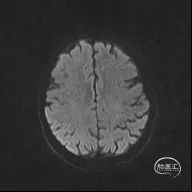

颅脑MR:脑内多发缺血灶、软化灶。